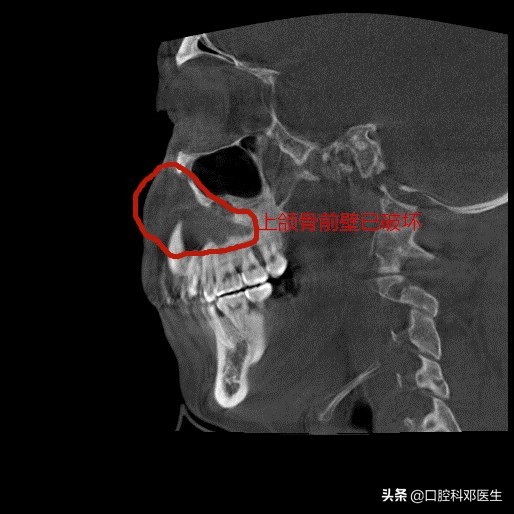

矢状位片

接诊的邓医生介绍:这位患者脸肿大是由于左侧上颌骨内一个埋伏多生的牙齿所引起的,由于牙齿无法正常萌出,经过时间的积累,从而诱发囊肿,囊肿一般都不痛不痒,越长越大,像鼓气球一样,逐渐破坏了周围的骨头,如破坏上颌骨前壁,就会突破至软组织,引起脸部肿大;如破坏牙槽骨,则会导致牙齿松动移位,引起牙根吸收疼痛等症状。